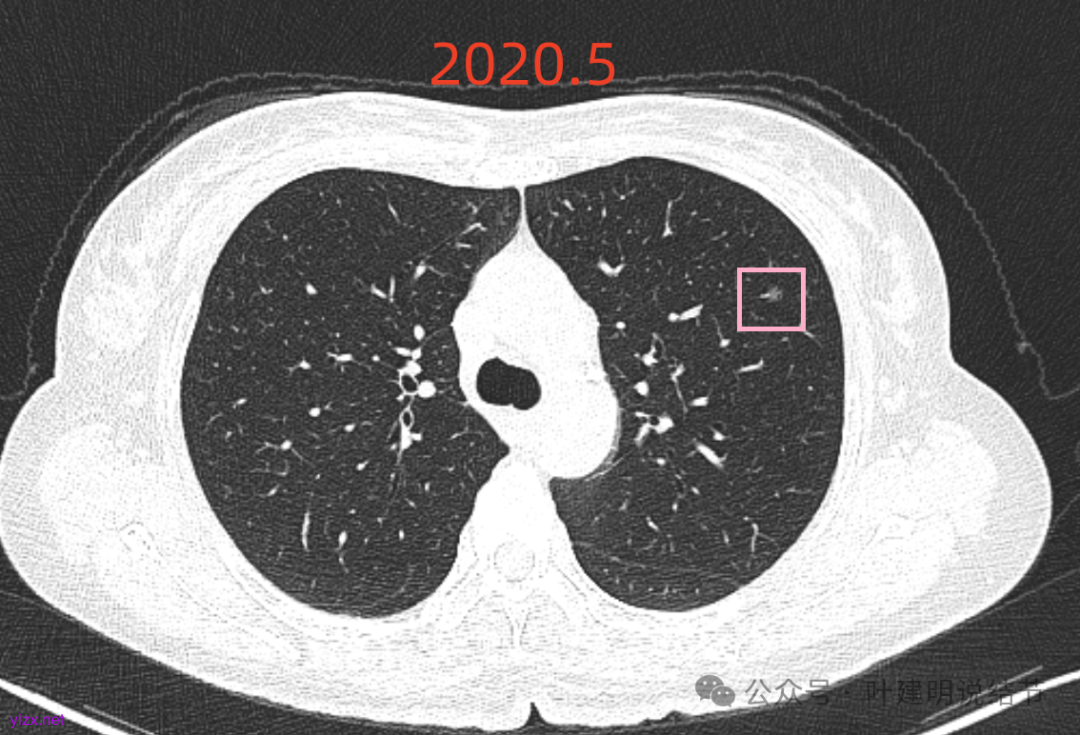

再看2020年5月时的主病灶以及两次对比的影像:

上图示对比,密度略有增加,但并不十分厉害。